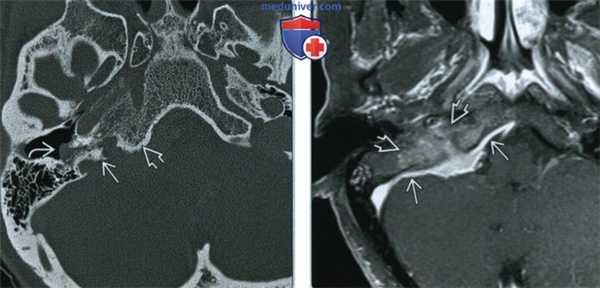

(Слева) В этом случае менингиомы яремного отверстия при аксиальной КТ в костном окне определяются характерные инвазивные склеротические изменения краев яремного отверстия и латеральной части ската. Менингиома прорастает в среднее ухо и при отоскопии может выглядеть как сосудистое объемное образование позади барабанной перепонки.

(Справа) При МРТ Т1 ВИ FS с КУ в аксиальной проекции определяется менингиома яремного отверстия в форме бляшки с «дуральными хвостами». Обратите внимание на отсутствие «пустот потока», поражение яремного отверстия и обширную инфильтрацию структур основания черепа.

(Слева) При КТ в костном окне в аксиальной проекции у пациента со шванномой яремного отверстия определяются классические изменения - ровные края расширенного яремного отверстия с тонким склеротическим ободком. Такая картина помогает дифференцировать это новообразование от других часто встречающихся новообразований яремного отверстия, в том числе от параганглиомы яремного гломуса и менингиомы.

(Справа) При МРТ Т2 FS в аксиальной проекции определяется гиперинтенсивное объемное образование правого каротидного пространства - разросшаяся шваннома яремного отверстия. Обратите внимание на характерные гиперинтенсивность и отсутствие «пустот потока».